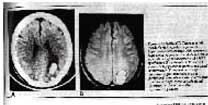

大谎号2:ECT不会导致脑损伤。一张图片将反驳。下面的插图(右边的MRI,CT留下,同一患者)描绘了ect的大出血。出血,大而小,在某些患者中导致永久性癫痫发作。

(Weisberg,L. Elliott,D和Mielke,D:电静脉治疗后脑出血(ECT)。1991年11月,神经内科V 41 P 1849.) |

另一项MRI研究记录了每次电击后血脑屏障的破裂和脑水肿(脑肿胀)。(Mander等人:《英国精神病学杂志》,1987:V 151,第69-71页)